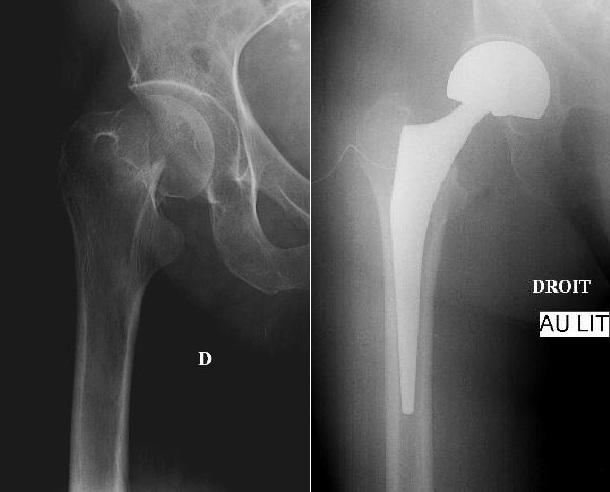

Quelle prothèse a été utilisée ici?

A

Fracture garden 4 ES fémur traitée par

prothèse intermédiaire de hanche